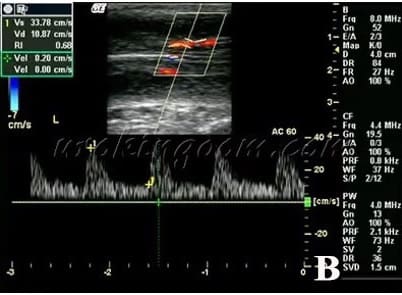

陰莖都卜勒超音波檢查特別用於評估觀察陰莖勃起功能,測量陰莖的血流參數,了解動脈血流情形,是否存在有陰莖動脈灌流不足造成動脈性勃起功能障礙或陰莖靜脈滲漏性勃起功能障礙等問題(圖1B)。

圖1: A) 陰莖曾經受傷或有佩諾尼氏症,導致海綿體或白膜產生鈣化及硬結

B) 也會影響海綿體結構及動脈血流灌流,容易產生血管性勃起功能障礙,包括陰莖靜脈血管滲漏。